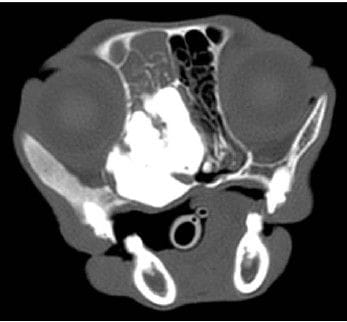

Computed tomographic image of the head of a 23-year-old domestic medium-hair cat examined because of a maxillofacial osteoma. The image was obtained prior to biopsy collection. The tumor was extensive and involved multiple bones of the nasal cavity. It occluded the nasopharynx, nasofrontal communication, and left nares.